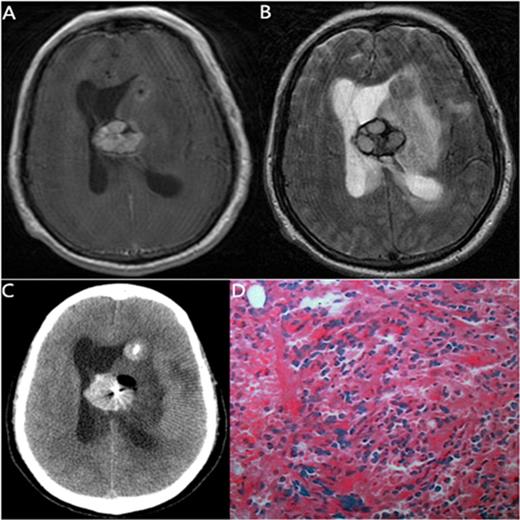

The MRI, biopsy site and pathology of a 60-year-old man with CMML

| 10 | 60/M | CMML | 57/4 y after allo-HSCT | Nausea, right limb weakness | MRI: a 2.5×2 cm2 lesion in left basal ganglia. | Leukemia | Chronic myelomonocytic leukemia | Died | |